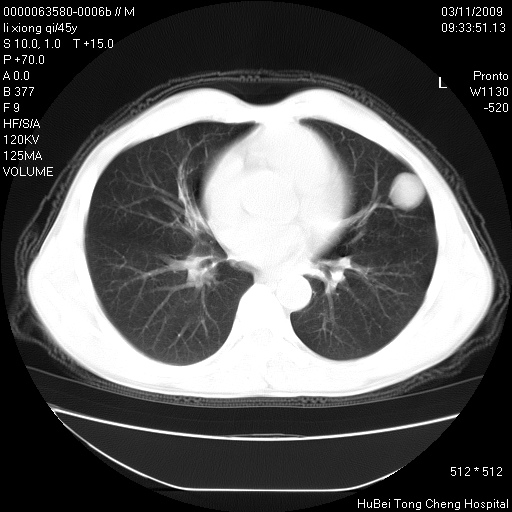

患者 男,45岁。胸痛,咳嗽伴痰中带血1月余。

临床诊断:肺结核?

胸部ct轴位平扫(层厚10mm,螺距1.5,重建间隔10mm),图像如下:

考虑肝癌肺转移